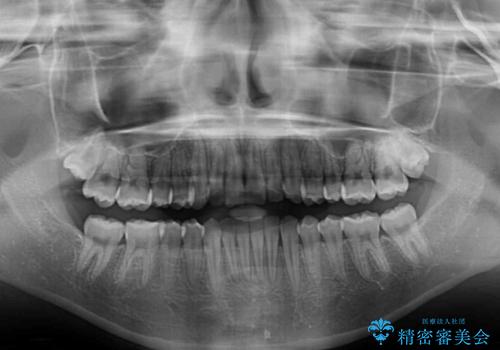

前歯のクロスバイト インビザラインによる矯正治療

- 前歯のクロスバイトを気にして来院された患者様です。

しっかりとインビザラインの装着時間を守っていただいたので、1年弱で矯正治療を終えることができました。